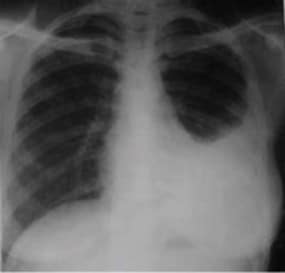

Chest X-rays of a 14-year-old male (BCG-vaccinated) with a positive tuberculin skin test and dextrocardia. Pneumonic infiltration was detected at the follow-up in the right lower zone of the chest X-ray after 50 days of isoniazid treatment

BCG (Bacille Calmette-Guérin) vaccine is a vaccine that is used to protect against tuberculosis. This vaccine is not widely used in the United States. However, it is often given to infants and small children in other countries where TB is common. It primarily affects the lungs but can also infect other parts of the body, such as the lymph nodes, bone, and brain.

The BCG vaccine is not effective in preventing TB, but it can significantly reduce the risk of infection and TB disease, particularly in children. It is essential in areas with a high prevalence of TB, as it can help to reduce the overall incidence in the population. In addition to its role in preventing TB, the BCG vaccine may also have some non-specific effects on the immune system, which may provide some protection against other infections.